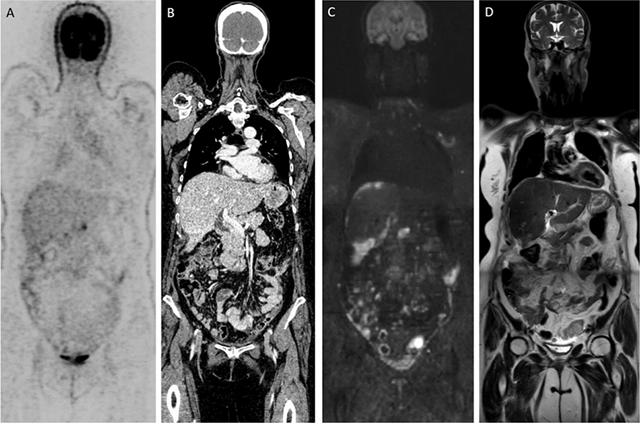

Magnetic resonance imaging (MRI) established its clinical importance by its superior contrast resolution and excellent soft tissue differentiation, beneficial for tumour detection, characterization, staging, and response assessment. Nowadays, MRI integrates novel functional imaging sequences diffusion-weighted imaging (DWI). DWI characterizes tumours characterization by probing differential water molecule displacements based on cellular microstructure differences. High tumour-to-background contrast is generated by combining heavy diffusion-weighting with background tissue signal suppression and the application of sequences tailored for whole body (WB) applications make DWI extremely useful for tumour staging. Studies have shown similar performance for WB-DWI/MRI to FDG-PET/CT for detecting retroperitoneal lymphadenopathy and distant metastases while WB-DWI/MRI shows better sensitivity than CT and FDG-PET/CT for peritoneal staging (Figure 1). As such WB-DWI/MRI enables better identification of tumoral infiltration of surgically critical sites including mesenteric root infiltration, small bowel, colon carcinomatosis, and unresectable distant metastases resulting in better prediction of (in)complete resection in patients eligible for debulking surgery.

Figure 1

Patient with diagnosis of ovarian cancer: (A, B) Time-of-flight FDG-PET/CT depicts limited number of peritoneal metastases. (C, D) Contrary, WB-DWI/MRI shows diffuse nodular and confluent carcinomatosis visible as b1000 hyperintense lesions on the (C) DWI-image.